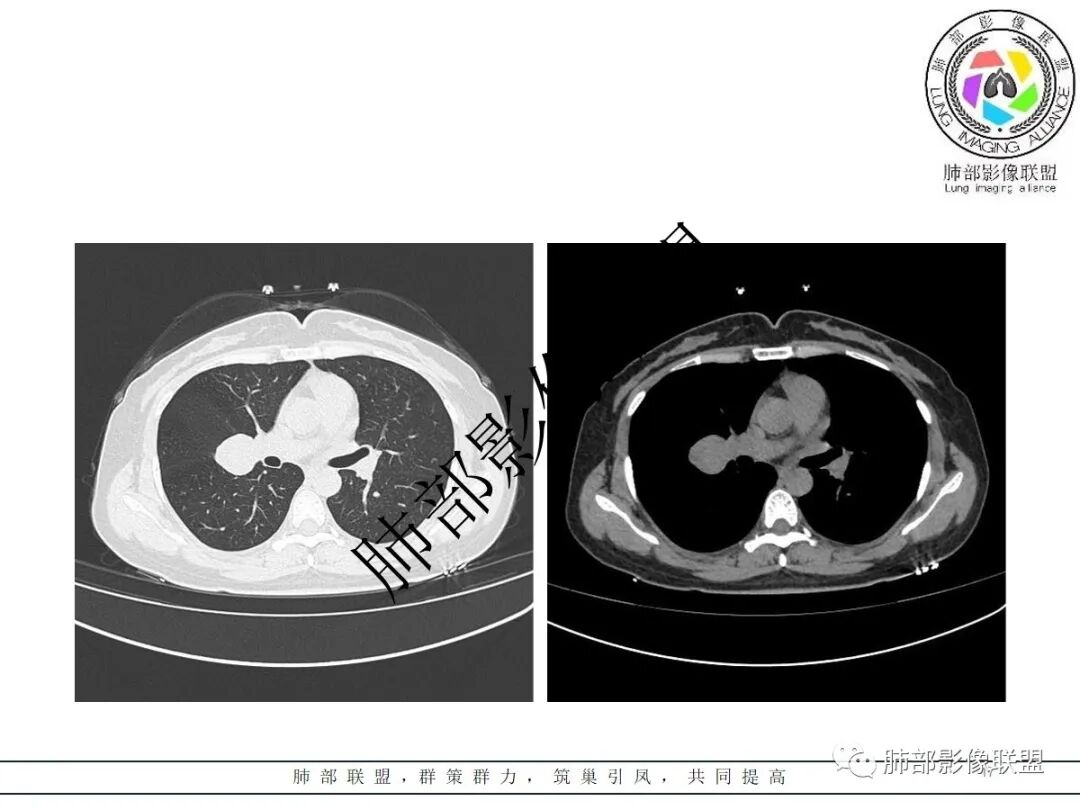

右肺门类圆形实性肿块,边缘光滑,无分叶毛刺,跨叶,推移血管,密度均匀,增强延迟强化相对明显,未见坏死及血管造影征。

2.右肺水平叶裂斜叶裂肺门交界区类椭圆形块影,表面光整,未见分叶毛刺及棘状突起,未见邻近结构牵拉。与邻近支气管无关联。

3.病灶密度均匀,未见液化坏死、钙化及脂肪低密度。轻度强化,可见纤细血管影蜿蜒穿行。右肺动脉推移变形,未见侵入或充盈缺损。

4.灶周未见磨玻璃晕或极低密度影环绕。右肺下叶背段胸膜下见微小实性密度结节影,边界清楚。

右肺门区类圆形肿块,跨叶,边缘光滑,密度均匀,血管贴边,推移,延迟强化,考虑PSP,鉴别CD

右近肺门类圆形肿块,边缘光滑,密度均匀,压迫邻近肺动脉,跨叶间裂,持续不均匀强化,内见血管影,肺门纵隔淋巴结未见肿大,考虑PSP,鉴别类癌。